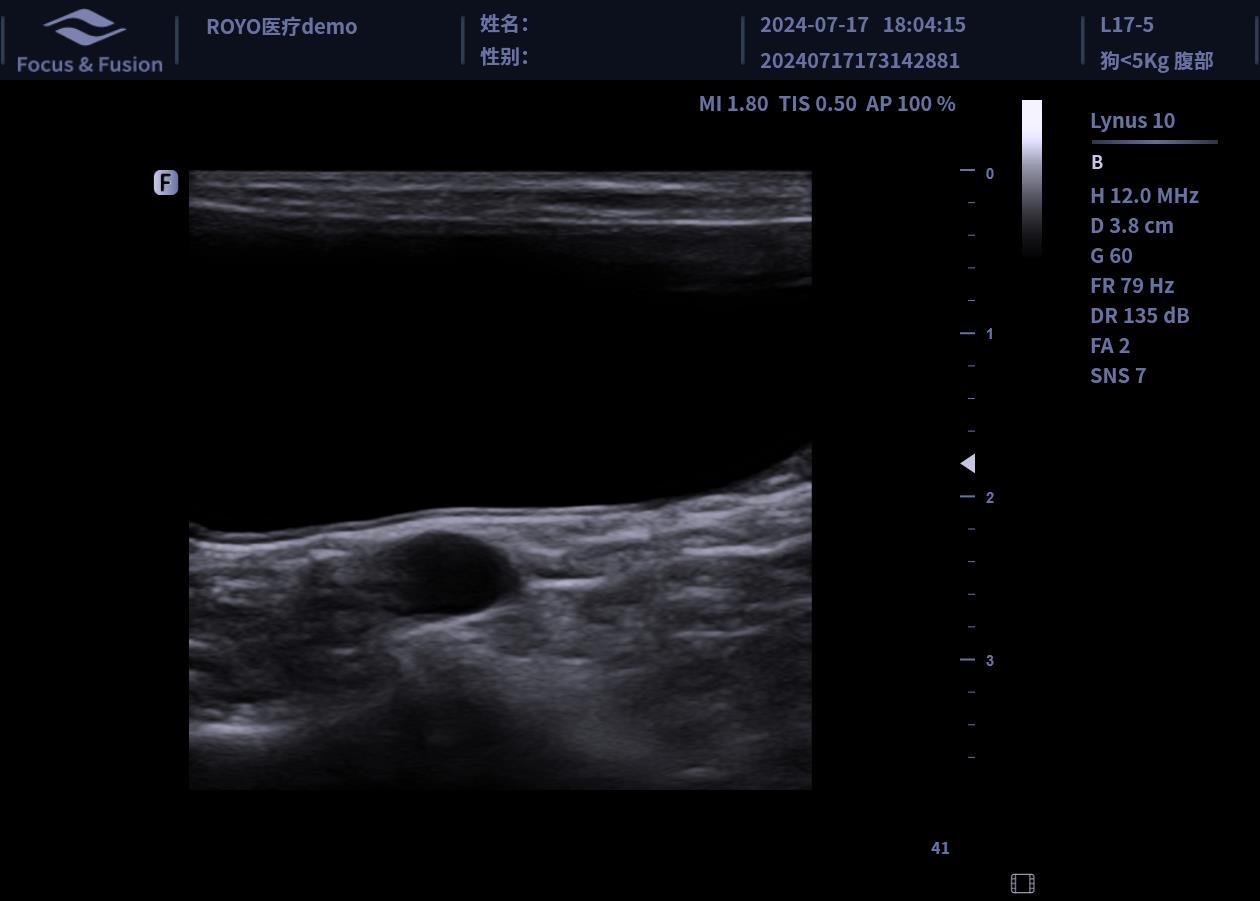

圖片展示

Image List